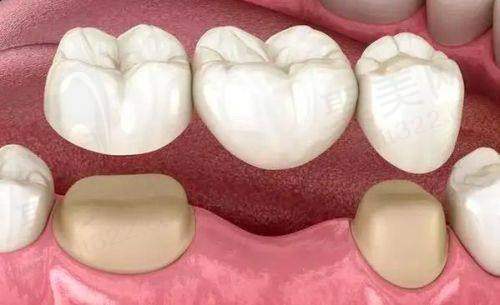

经历了烤瓷牙的痛苦后,我又开始了我的重新开始。通过医生的建议,我选择了种植牙修复,这让我逐步走出了被骗做烤瓷牙的阴影。虽然种植牙的过程复杂且费用不菲,但我相信这是我值得拥有的健康投资。

种植牙的技术在近年来取得了显著的发展,可以较大程度贴合自然牙齿。相比于烤瓷牙,种植牙的成效更加持久,使用寿命可达十年以上,甚至能够终身使用,这让我倍感安心。了解这一点后,我开始重拾对笑容的信心。

更重要的是,种植牙不会改变我口腔的结构,它更注重维持我的咬合与发音,使我可以尽情享受美丽的生活。当我再次能够品尝食物的乐趣时,我感到无比欣慰。